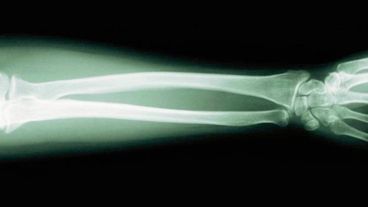

El osteosarcoma es un tipo de cáncer óseo que afecta sobre todo a varones con edades comprendidas entre los 10 y los 30 años. De hecho, elosteosarcoma se corresponde con el cáncer de hueso primario más común en niños y adolescentes. Y si bien la supervivencia a los cinco años es de únicamente un 15-30% en las fases avanzadas –es decir, cuando el tumor ya se ha extendido a otros órganos–, puede ser detenido, según concluye un estudio llevado a cabo por investigadores del Centro Oncológico Princesa Margarita de Toronto (Canadá) y publicado en la revista «Science Translational Medicine».